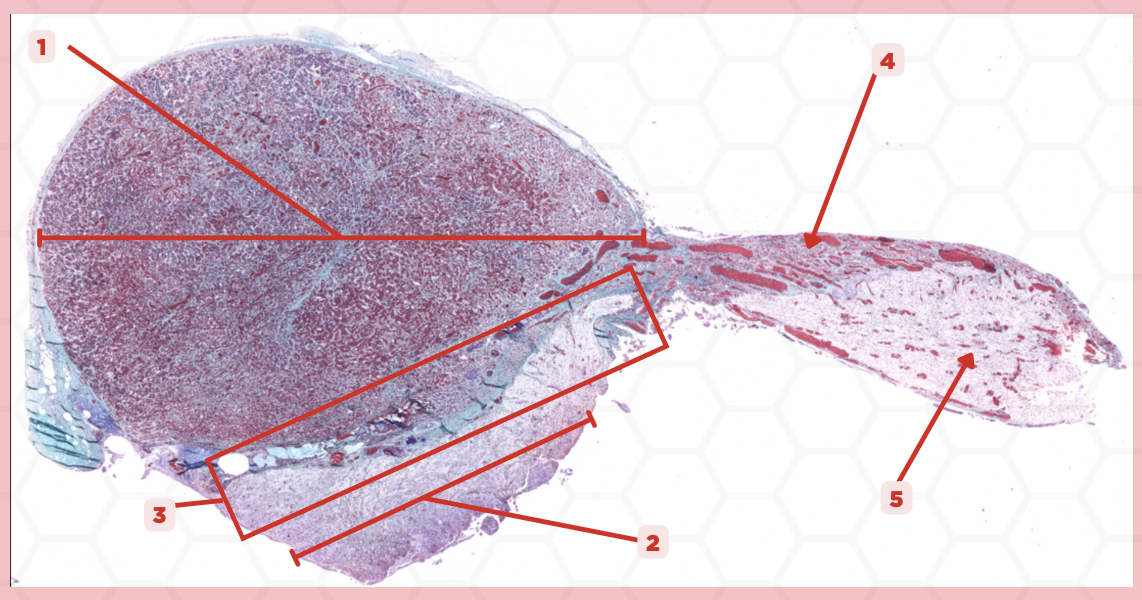

Pituitary

Identify the specimen.

Anterior Lobe

Identify the structure labeled as 1.

Posterior Lobe

Identify the structure labeled as 2.

Intermediate Lobe

Identify the structure labeled as 3.

Pars Tuberalis

Identify the structure labeled as 4.

Pituitary Stalk

Identify the structure labeled as 5.